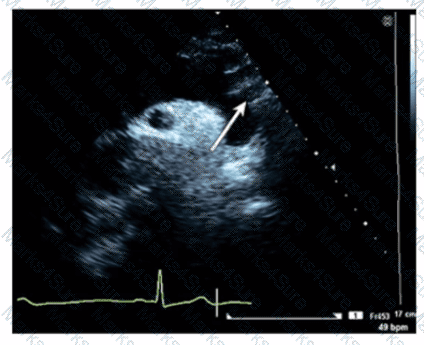

A patient presents with tender, red lesions on their fingers and toes (Osier nodes). Which finding is most likely?

Which type of mass is typically attached to the fossa ovalis of the left atrium?